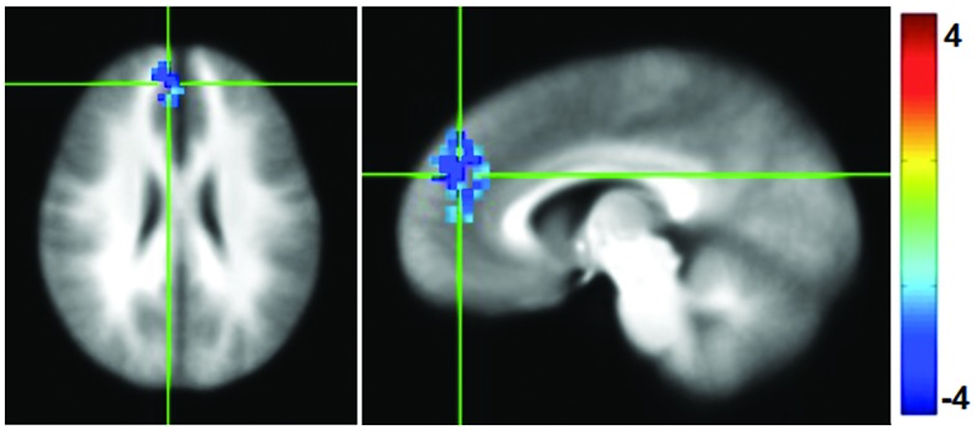

训练项目主要通过正念,来增强身体意识和提高我们对身体信号进行响应的能力,特别是在面对压力的情境下。研究结果显示,经过七周密集正念训练后,运动员有了更高的内在感知和觉察、更强的正念意识以及更好的情绪识别能力。运动员在面对呼吸负荷的任务时,岛叶和前扣带皮层(ACC)等大脑区域的激活增强。也就是说,他们的自我调节、复原力、以及描述和识别情绪的能力都得到了提到。fMRI大脑影像结果同步证明了参与者的这些改善。数据显示,他们大脑内部与内在感受、觉知和认知相关的区域,如岛叶和ACC,激活增加,这些区域都主要是处理身体感觉和管理情绪反应的。他们的后扣带皮层(PCC)与其他大脑区域之间的静息功能连接减少,这就是说,能更好的在不同负责认知控制的大脑网络之间切换的能力提高,从而有助于提高专注力和情绪调节。